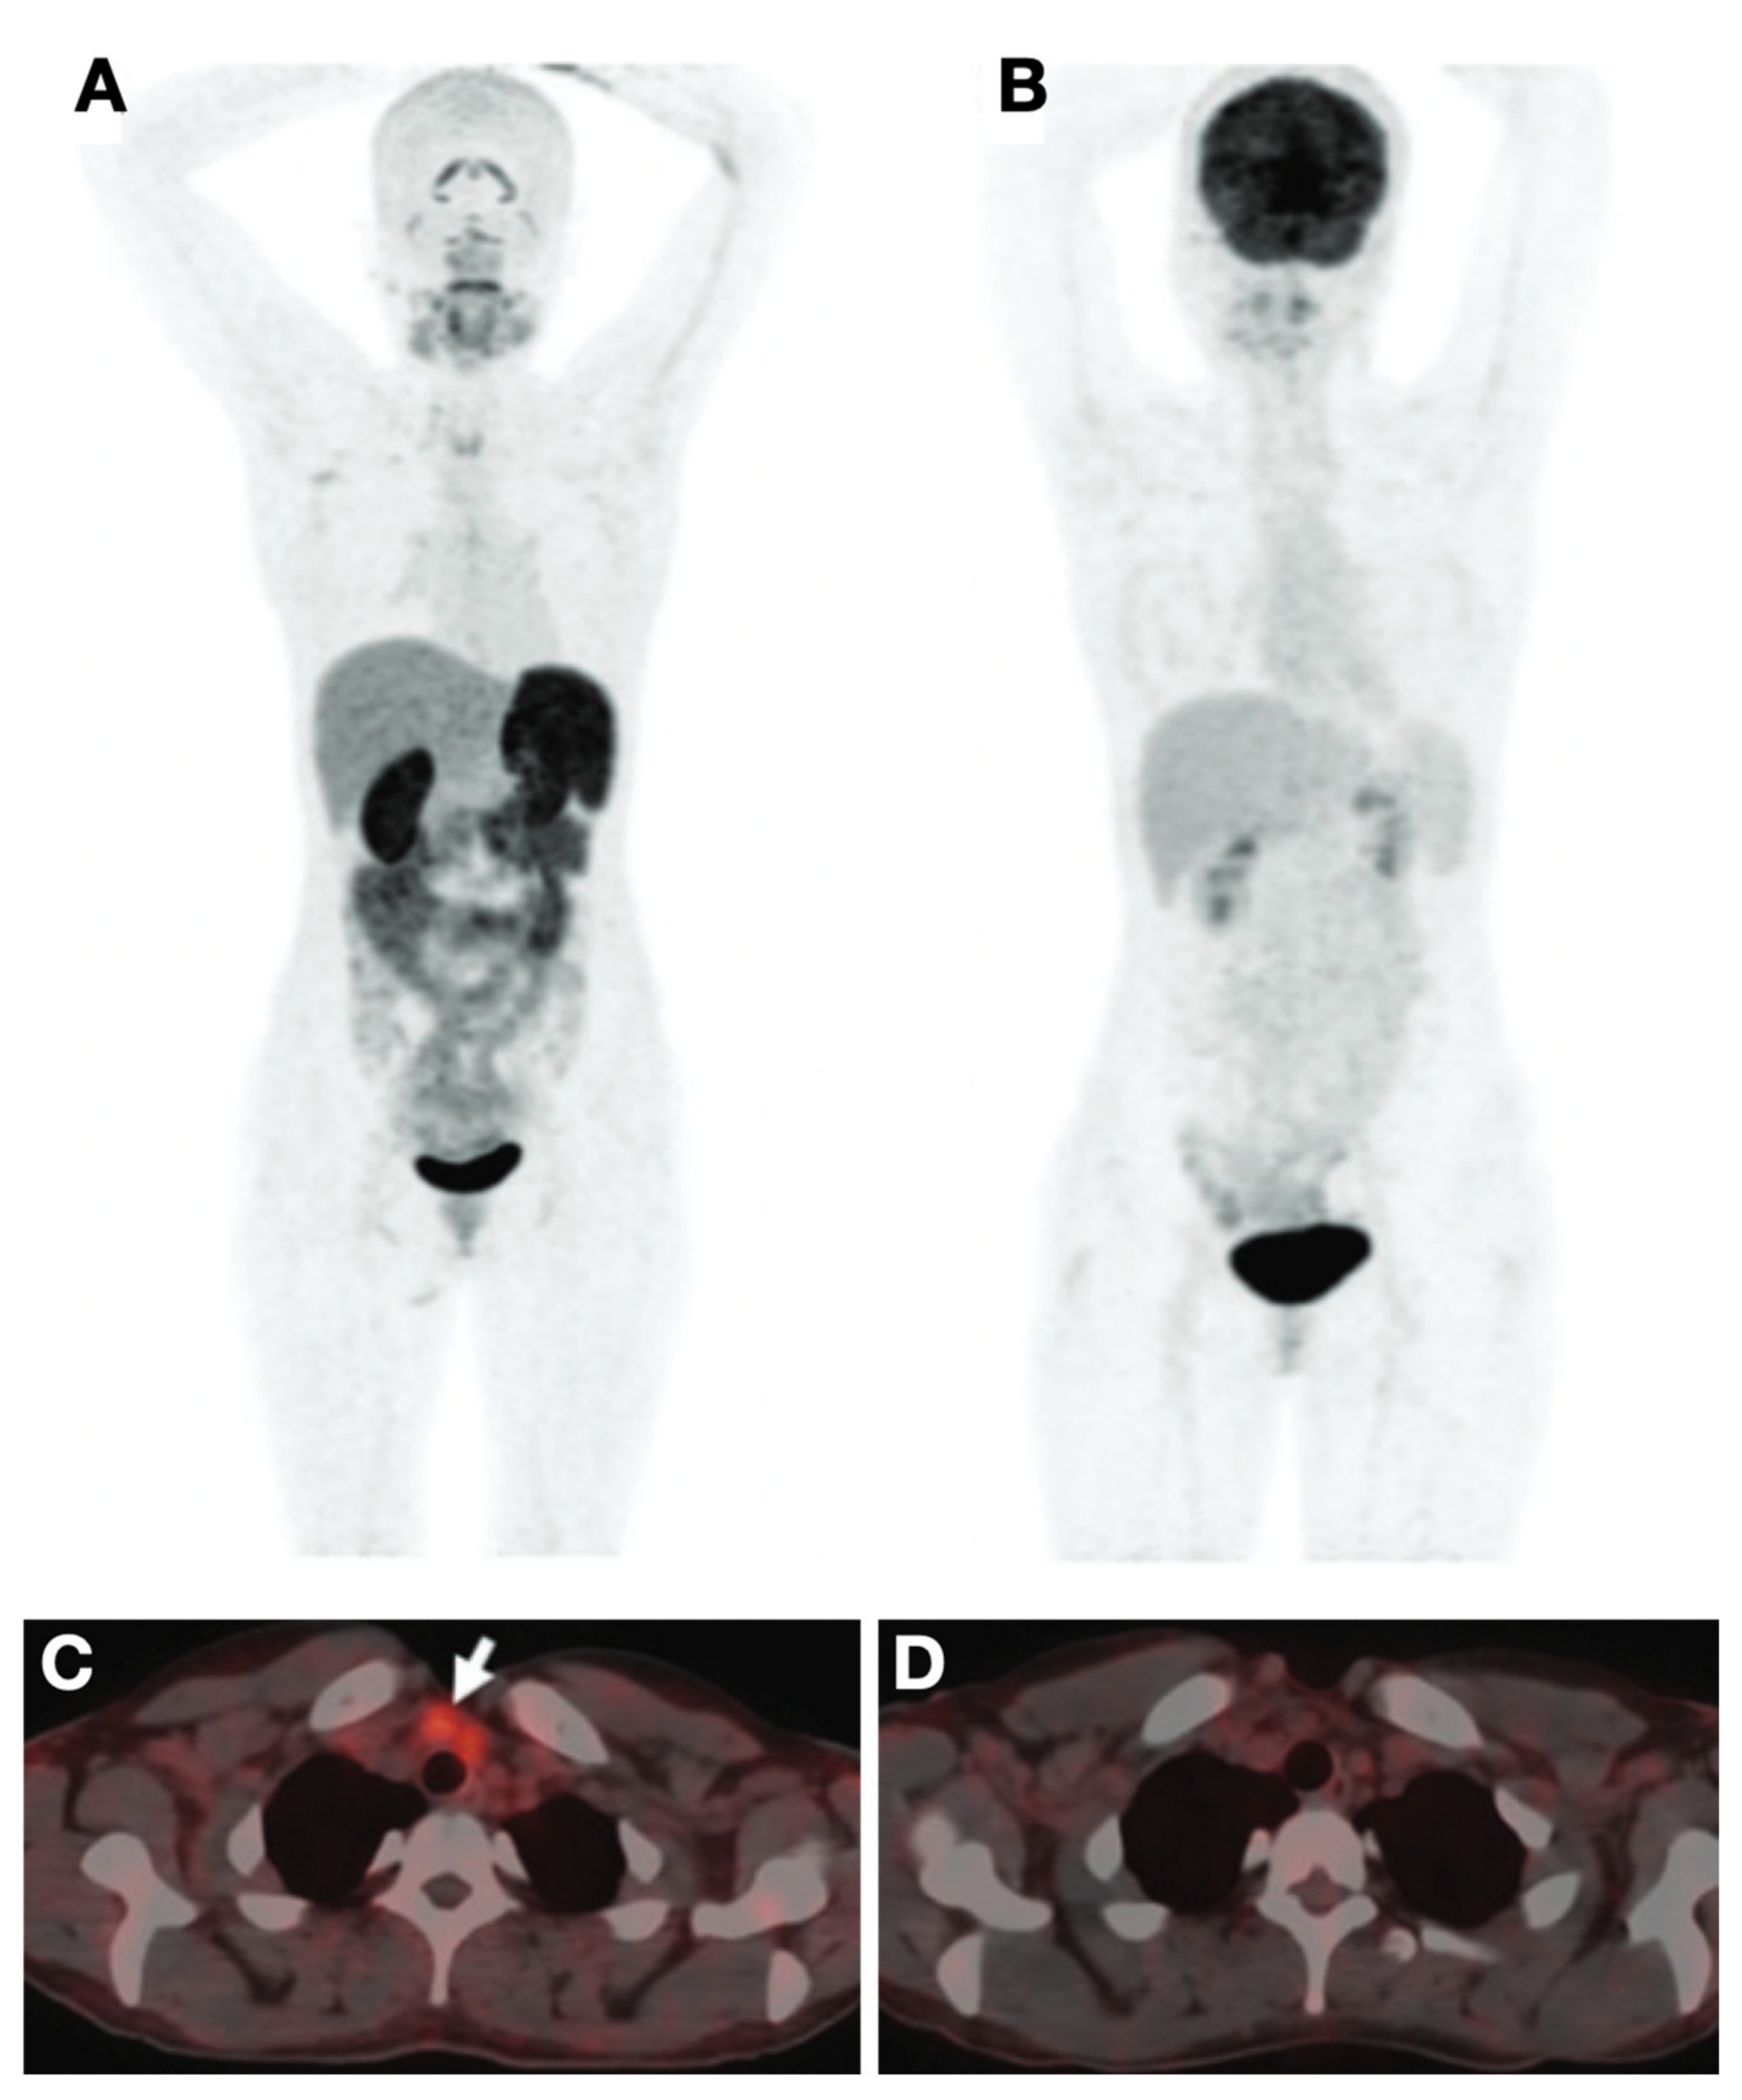

- Parihar, A.S.; Mittal, B.R.; Kumar, R.; Shukla, J.; Bhattacharya, A. 68Ga-DOTA-RGD2 Positron Emission Tomography/Computed Tomography in Radioiodine Refractory Thyroid Cancer: Prospective Comparison of Diagnostic Accuracy with 18F-FDG Positron Emission Tomography/Computed Tomography and Evaluation Toward Potential Theranostics. Thyroid Off. J. Am. Thyroid Assoc. 2020, 30, 557–567. [Google Scholar] [CrossRef]

- Parihar, A.S.; Sood, A.; Kumar, R.; Bhusari, P.; Shukla, J.; Mittal, B.R. Novel Use of 177Lu-DOTA-RGD2 in Treatment of 68Ga-DOTA-RGD2-Avid Lesions in Papillary Thyroid Cancer with TENIS. Eur. J. Nucl. Med. Mol. Imaging 2018, 45, 1836–1837. [Google Scholar] [CrossRef]